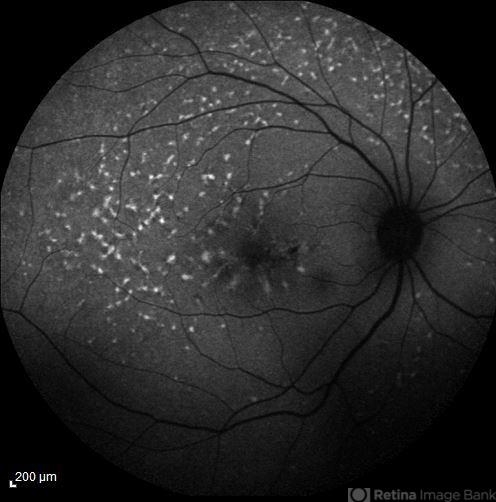

- fundus flavimaculatus, retinal flecks, choroidal neovascularization (CNV), fundus autofluorescence (FAF)

- FAF image of the right eye of a 35-year-old woman with subfoveal CNV secondary to fundus flavimaculatus .